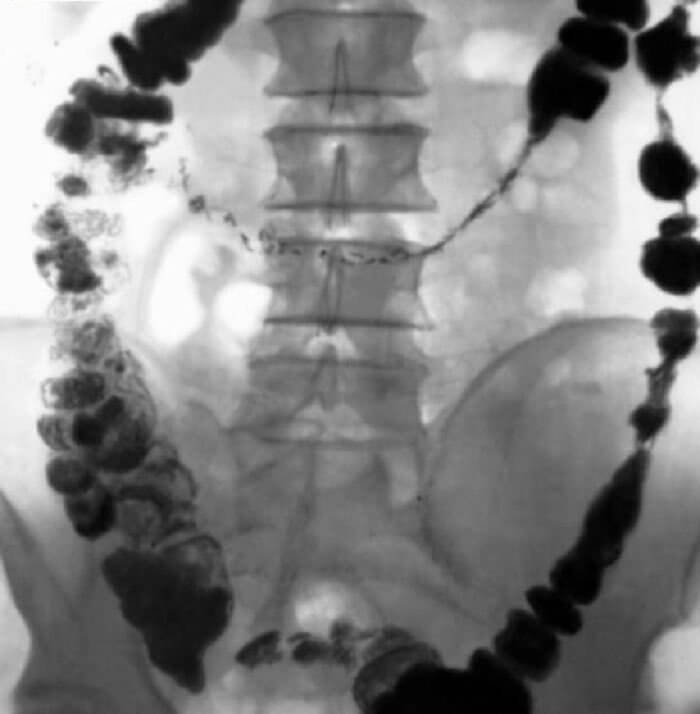

Каловый камень представляет собой конкремент, образующийся в кишечнике из-за нарушения пищеварения и недостатка жидкости. Врачи отмечают, что симптомы, такие как боли в животе, запоры и чувство тяжести, могут указывать на наличие этого образования. Диагностика включает в себя рентгенографию, ультразвуковое исследование и колоноскопию, что позволяет точно определить размер и местоположение камней.

Для диагностики незначительных камневых новообразований требуется проведение следующих видов исследований:

- колоноскопия;

- эхография;

- рентгенографическое;

- ультразвуковое;

- компьютерная томография брюшной полости.

Такая комплексная диагностика дает специалисту возможность не только поставить точный окончательный диагноз, но еще и опередить размеры каловых камней, их точную локализацию. На основании полученных результатов пациенту назначается оптимальное, наиболее эффективное для конкретной клинической ситуации лечение!